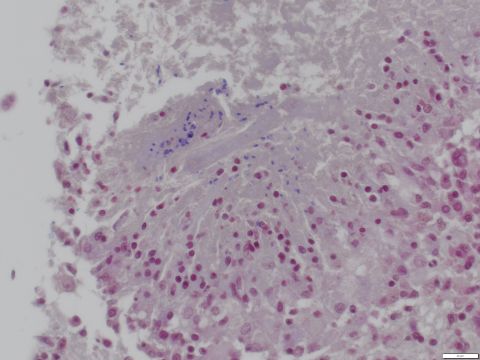

Species: Rabbit

Brain

Focal granulomatous and necrotizing encephalitis with intralesional gram positive microsporidian spores.

Cause of death was predator trauma. Unrelated to E. cuniculi infection which was incidental.